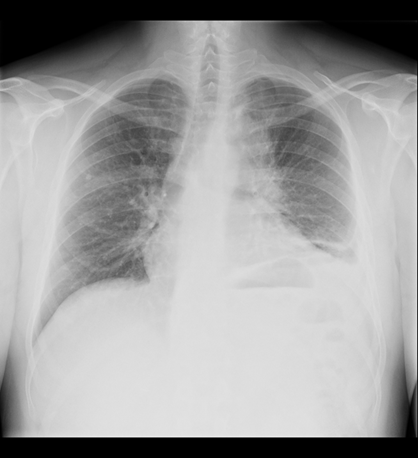

Rx de tórax

Haz click en las imágenes para verlas ampliadas

HALLAZGOS RADIOLÓGICOS

A

Ensanchamiento del cayado aórtico; ascenso de la cúpula diafragmática izquierda y obliteración del seno costofrénico.

B

Ensanchamiento del cayado aórtico; ocupación de la base torácica por una lesión con nivel hidroaéreo.

C

Pérdida de la silueta del cayado aórtico; ascenso de la cúpula diafragmática izquierda y obliteración del seno costofrénico.

D

Pérdida de la silueta del cayado aórtico; ocupación de la base torácica por una lesión con nivel hidroaéreo.